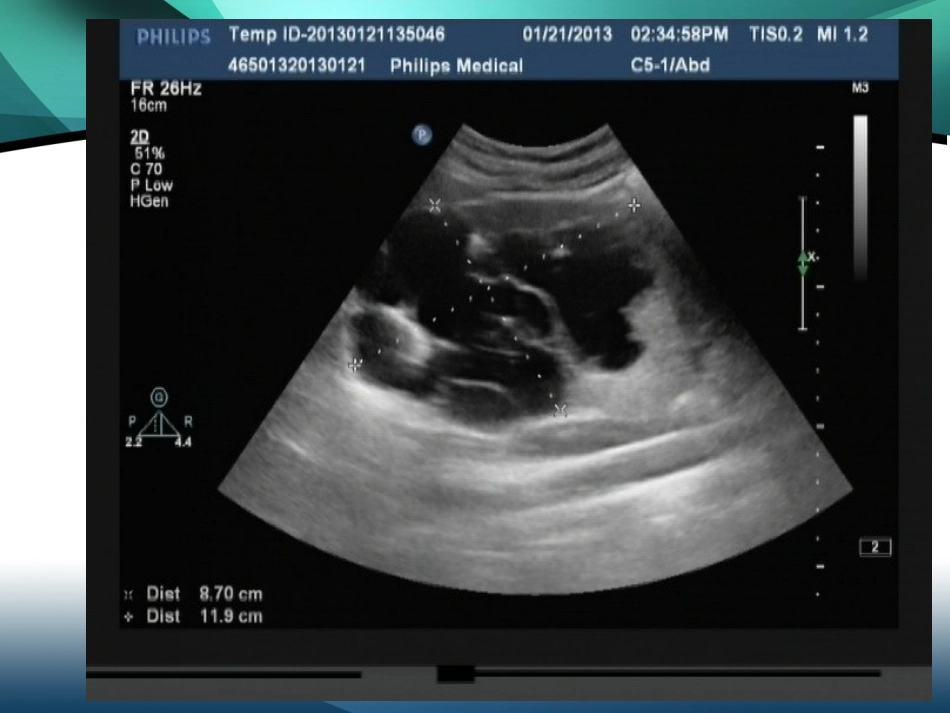

20132013年年22月月2424日日特殊及疑难病例讨论病例•女23岁•无痛性肉眼血尿重复肾•重复肾是较常见的肾、输尿管先天畸形,发病率约1500:1。•重复肾多数融合为一体,多数不能分开,表面有一浅沟,但肾盂、输尿管上端及血管分开。•重复输尿管可为完全型,亦可为不完全型,可开口于膀胱内,亦可异位开口于尿道、前庭或阴道。病因•在人胚胎第六周时,中肾管末端通入泄殖腔处,向背侧突出一小的盲管,称为输尿管芽。输尿管芽发育成肾盂,分支形成肾盏、再分支形成小盏、集合管。如分支过早,则形成重复的输尿管畸形。分支的高低及多少,可决定形成完全或不完全,双重或多支输尿管畸形。•重复输尿管常伴发重复肾脏。重复肾多数结合成为一体,有一共同被膜,表面有一浅沟,但肾盂输尿管及血管都各自分开。重复肾脏完全分开者,甚为少见。临床表现•1.不完全的重复输尿管畸形,或完全型的重复输尿管畸形,输尿管均开口于膀胱内,且没有合并症。这类病例完全没有临床症状,只有在进行泌尿系全面检查时才被发现。此类病人约占60%。•2.重复肾伴有合并症,出现肾盂炎、肾结石、结核、肿瘤、积水等症状表现而进行泌尿系全面检查时为所发现。•3.为完全型的双重输尿管畸形,输尿管开口于外阴前庭、阴道……等处。致患者自幼年就有遗尿史,夜晚尿湿床铺,白天也经常短裤不干;但患者又有正常的排尿活动。如有此种病史,仔细检查外阴,常能察见异常输尿管开口。即使找不到异常输尿管开口,静脉肾盂造影亦常能证实此种先天畸形问题。【影像学诊断】•静脉泌尿造影可清楚显示功能良好的重复肾及双输尿管畸形,对功能不良的重复肾则容易误诊•B超可显示功能良好的重复肾畸形,但对双输尿管及合并积水的重复肾则显示欠佳且超声难以发现重复输尿管的异位开口位置,且需与肾上极囊肿及双肾盂畸形鉴别•CT检查可清晰显示重复肾畸形及合并积水的双输尿管,能更清楚的显示重复肾的内容,同时CT连续层面观察可确定输尿管的异位开口,但对无扩张的重复输尿管显示不够清晰,直观。单侧肾四肾盂四输尿管囊性肾癌•临床比较少见的肾脏囊性肿瘤,约占肾癌总数的4%~15%,发病年龄一般在40岁以上,起病比较隐匿,症状不典型,临床表现以腰部不适或疼痛者居多,较少出现肉眼血尿和腹部包块。囊性肾癌的超声改变•可分为三型:•多房囊肿型•单房囊肿型•囊实型•病灶囊壁和/或分隔不规则增厚,部分囊壁和分隔伴弥漫性粗细不均钙化。有的囊壁薄而规整,超声误诊为肾囊肿。多房性肾囊肿。囊腔透声差,呈细密点状弱回声及不均质片状高回声。彩色多普勒显示大多数增厚的囊壁、分隔和实性部分可探及动脉血流信号。谢谢!谢谢!